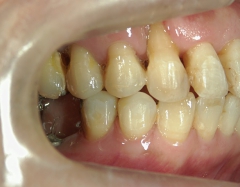

矯正歯科(全顎ワイヤー矯正)治療後

矯正歯科 治療後